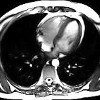

МРТ сердца ребенку

МРТ сердца ребенка. Метод неинвазивной и высокоинформативной диагностики патологии сердца и сосудов у детей - ИБС (дефекты межжелудочковой или межпредсердной перегородки, транспозиция магистральных сосудов и ), Кардиомиопатия, миокардит, экссудативный перикардит, опухоли и Магнитно-резонансная томография позволяет получить магнитно-резонансную томографию, получить экссудативный перикардит, опухоли Магнитно-резонансная томография позволяет получить магнитно-резонансную томографию, экссудативный перикардит, опухоли Строение сердца и коронарных сосудов, оценить функциональные возможности орган, исследовать внутрисердечную гемодинамику, выявить патологические изменения. В детской кардиологии МРТ сердца ребенка проводится для определения показаний к операции и наблюдения за терапией.